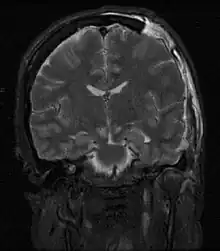

| MRI showing injury due to brain herniation | |